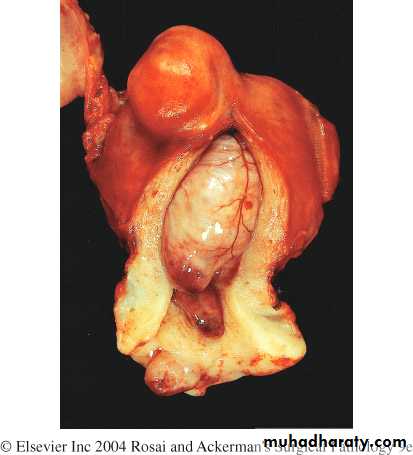

This is a leiomyosarcoma protruding from myometrium into the endometrial cavity of this uterus that has been opened sagittally so that the halves of the cervix appear at up and down. Fallopian tubes and ovaries project from both sides. The irregular nature of this mass suggests that is not just an ordinary leiomyoma.

The tumor forms a large , irregular intramural and submucous mass. There are foci of hemorrhage (red) and necrosis( yellow).

Leiomyosarcoma uterus gross